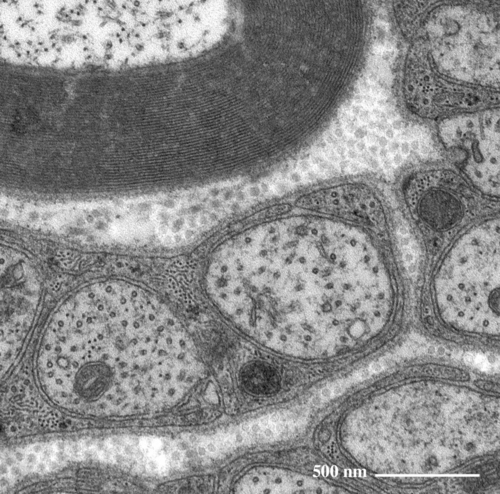

有髄神経(上)と無髄神経(下)の拡大像

有髄神経髄鞘の拡大像

無髄神経の拡大像